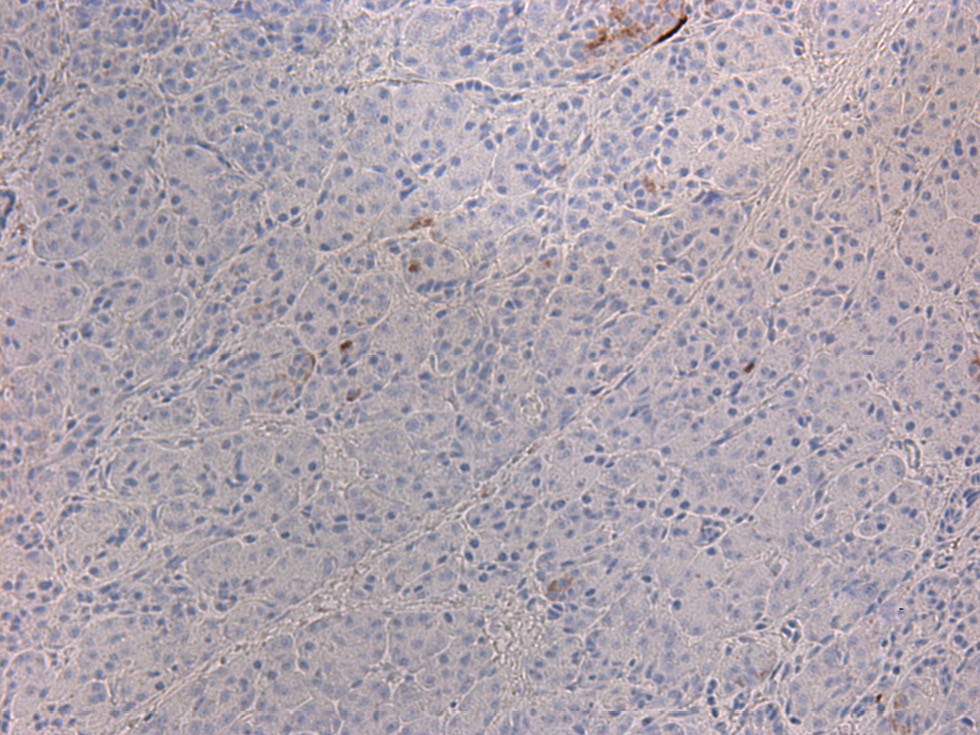

Несмотря на относительную эугликемию у части больных на фоне лечения октреотидом или диетотерапии, всем пациентам было проведено хирургическое вмешательство. Показания к оперативному лечению были обусловлены высоким риском развития гипогликемии на фоне пропуска приема пищи, тахифилаксией при применении октреотида, а также возможностью полного излечения после проведения резекции фокуса [23]. Большей части (25/31) детей выполнена резекция участка аденоматоза с проведением интраоперационной гистологической диагностики для оценки края иссечения (рис. 4). Проведение субтотальной панкреатэктомии пациентам с фокальной формой ВГИ было связано с отсутствием возможности проведения полной предоперационной диагностики, в частности ПЭТ/КТ с 18F-ДОФА на момент обследования.

Рис. 4. Гистологическое исследование ткани поджелудочной железы у пациента с фокальной формой ВГИ.

а – фокус гиперсекреции инсулина, метаплазия островков (окраска гематоксилином и эозином, ×20); б – выраженная экспрессия инсулина в фокусе при проведении иммунногистохимии; в – ткань поджелудочной железы вне фокуса гиперсекреции инсулина (окраска гематоксилином и эозином, ×200); г – низкая экспрессия инсулина вне фокуса при проведении иммунногистохимии.